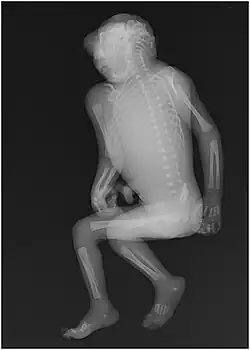

Anencefalie[1] is een neuralebuisdefect, een aandoening aan de neurale buis die ontstaat tijdens de embryonale ontwikkeling. Uit deze buis ontstaat later het zenuwstelsel. Bij anencefalie sluit de bovenkant van de neurale buis niet goed. Dit kan resulteren in een verminderde ontwikkeling van de hersenen. Soms ontwikkelen deze zich helemaal niet. Meestal is de hersenstam wel ontwikkeld, maar ontbreekt het cerebrum (de grote hersenen).